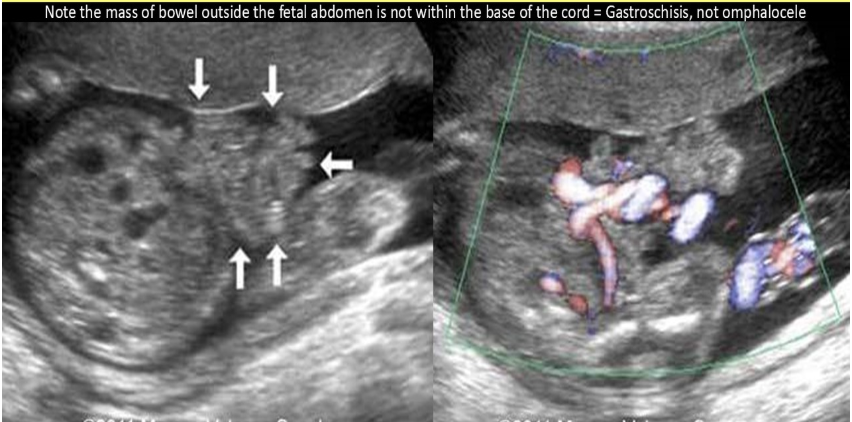

![<p>an abd wall abn that occurs w/abd contents <strong>herniating <em>through abd wall</em> [as in not covered]</strong>layers outside the fetus is</p><p>.</p><p>a) allantoic cyst</p><p>b) omphalocele</p><p>c) gastroschisis</p><p>d) cloacal extrophy</p>](https://knowt-user-attachments.s3.amazonaws.com/fd44542a-011f-4c00-afe9-6ec2cde36bed.png)

an abd wall abn that occurs w/abd contents herniating through abd wall [as in not covered]layers outside the fetus is

.

a) allantoic cyst

b) omphalocele

c) gastroschisis

d) cloacal extrophy